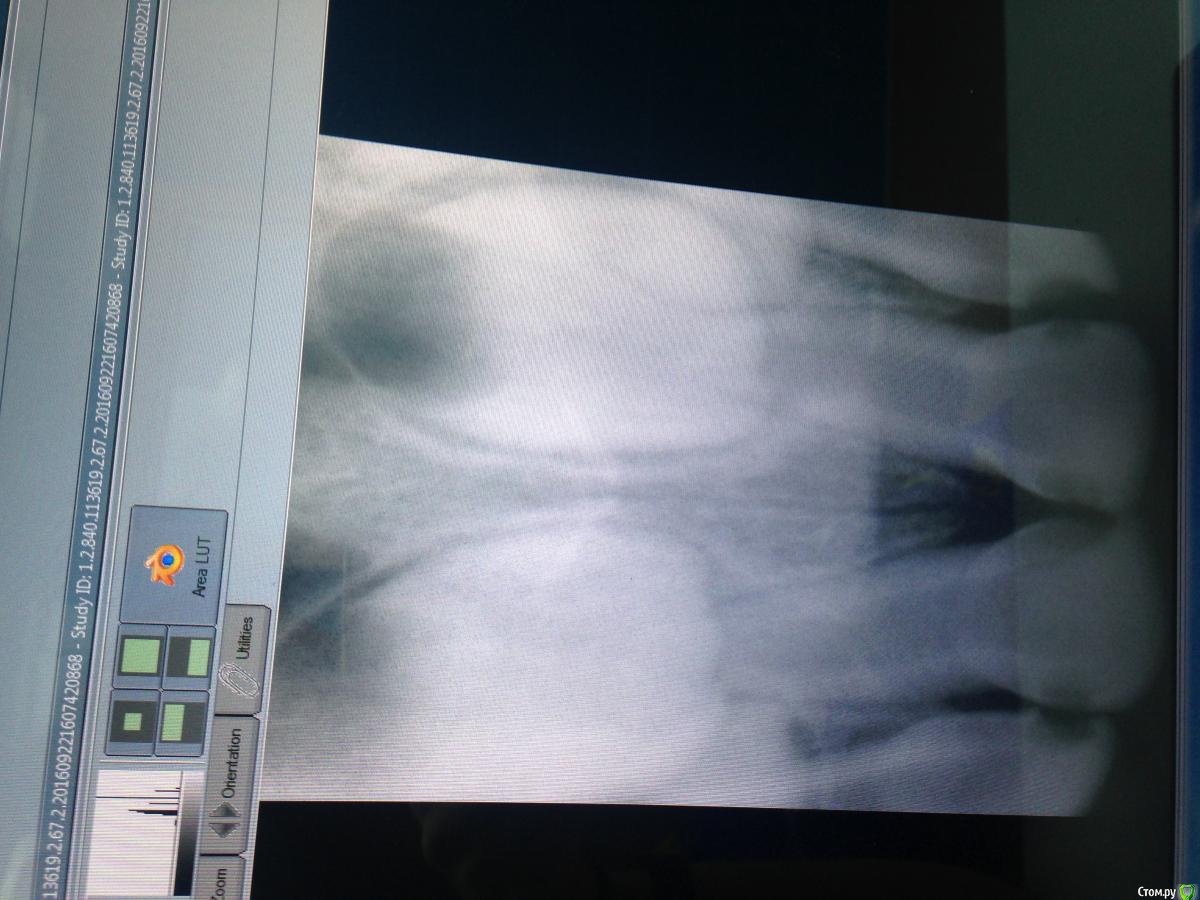

Malina11v Опубликовано 22 сентября, 2016 Поделиться Опубликовано 22 сентября, 2016 Девочке 3 года, жалоб нет, как думаете, это уже пульпиты или есть вероятность пролечить по кариесу? Пришли с жалобами на кариес на зубах, хотят реставрации сделатьНикогда раньше не делала рестоврации на молочных зубах, знаю, что часто скалываются, поэтому переживаю Ссылка на комментарий